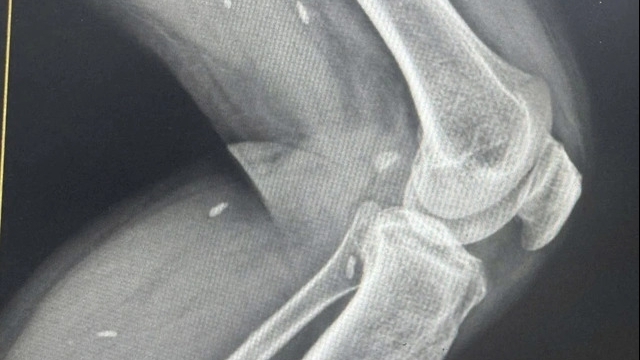

Tại đây, các bác sĩ tiếp tục tìm nguyên nhân gây bệnh bằng chẩn đoán hình ảnh như chụp cắt lớp, cộng hưởng từ, siêu âm nội soi tuyến tụy tìm u tụy, đồng thời xét nghiệm hormone ở các tuyến nội tiết khác. Kết quả cho thấy tăng gastrin trong máu, tăng các hormone khác như PTH, prolactin…

Tiến sĩ Khanh chia sẻ, hormone gastrin kích thích tăng tiết axit gây loét dạ dày và tá tràng. 20-25% khối u tiết gastrin nằm tại tụy, 50-88% khối u tiết gastrin nằm rải rác ở nơi khác ngoài tụy và 70-100% hội chứng Zollinger Ellison liên quan tới đa u tuyến nội tiết. Sau hội chẩn đa chuyên khoa, bác sĩ kết luận anh Tiến mắc đa u tuyến nội tiết (MEN 1). Bệnh lý hiếm gặp với tỷ lệ khoảng 3 – 20 trường hợp mắc bệnh/100.000 dân.